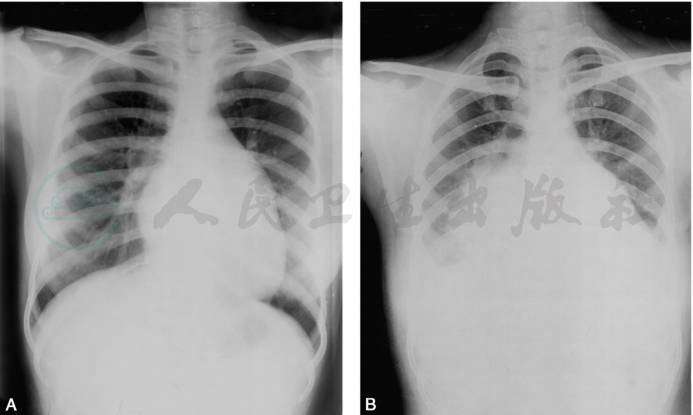

单纯二尖瓣狭窄时,左心室不大或缩小,表现为左心缘第四弓缩短变直。还可见主动脉节缩小。绝大多数患者存在不同程度的肺循环高压,是判断病变程度的重要指标。病变早期可只有肺淤血,表现为上下肺静脉管径比例失调。但临床病例多为混合性肺循环高压,X线表现为相应的轻、中、重度肺静、动脉高压征象,仅表现为肺动脉高压者并不多见(图1)。

图1二尖瓣狭窄

心影呈“二尖瓣型”,左心房、右心室增大(A),二尖瓣狭窄合并关闭不全时,左心室亦有增大,伴有少量胸腔积液(B)

引自:实用放射学.第4版.ISBN:978-7-117-28542-1.主编: